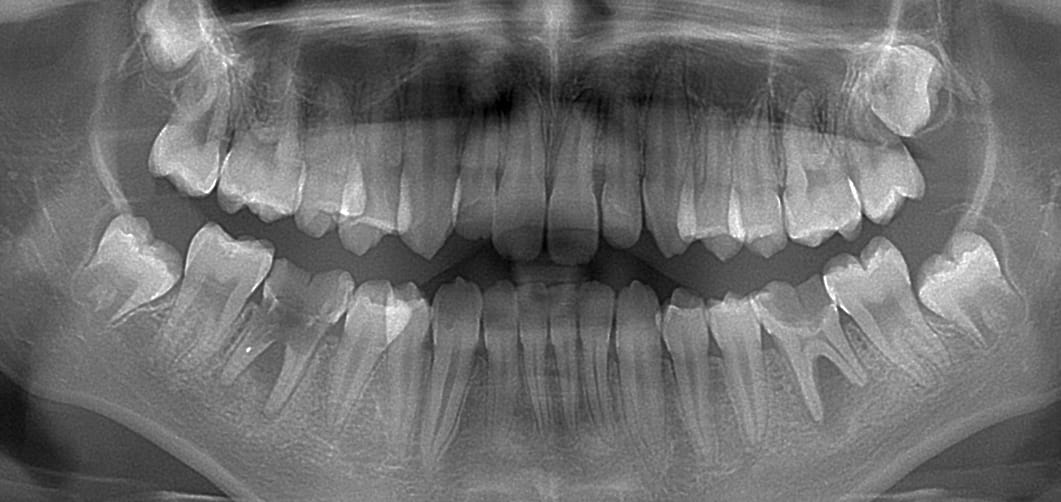

C’est pas mignon ces chicots qui luttent, luttent, luttent contre la carie à faire de la dentine réactionnelle ?

Mention spéciale pour 75 qui se bat encore alors que la pulpe est à nue.

Enfant de douze ans, motif de la consultation: "aucun dentiste dans mon coin ne prend d'enfants, ça fait deux ans qu'on cherche, on prend des rdv mais ils se font annuler au dernier moment parce que ne prend pas les enfants"

C'est bête, les racines des 7 sont complètement formées, l'orthodontiste va galérer comme un putois pour combler les espaces.

Au passage, enfant parfaitement compliant, je vois pas trop où aurait été la difficulté de lui faire endo + couronne sur 36 46 y a un an.